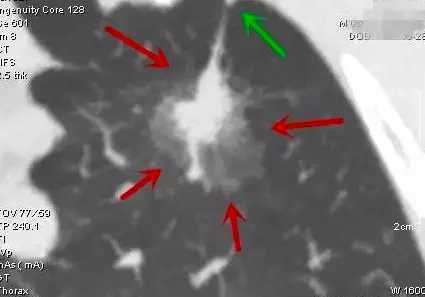

第四类:浸润性腺癌(IAC)(表现为混合磨玻璃结节)

意义:会转移与复发的肺腺癌,可能会淋巴结转移或血行转移。但实性部分若甚少,则转移可能性很小,实性部分占比越大越危险。

典型表现:混合磨玻璃结节,实性部分有收缩纠集感,边上磨玻璃部分可有细毛刺征(边缘不锐利,有细小锯齿状)。如下图:

浸润性腺癌(部分成分磨玻璃),绿色箭头示胸膜牵拉

手术与否:建议立即手术,不能等待!基本上都需要肺叶切除加淋巴结清扫。实性成份少或者肺功能受限也可考虑肺段切除及淋巴结采样。